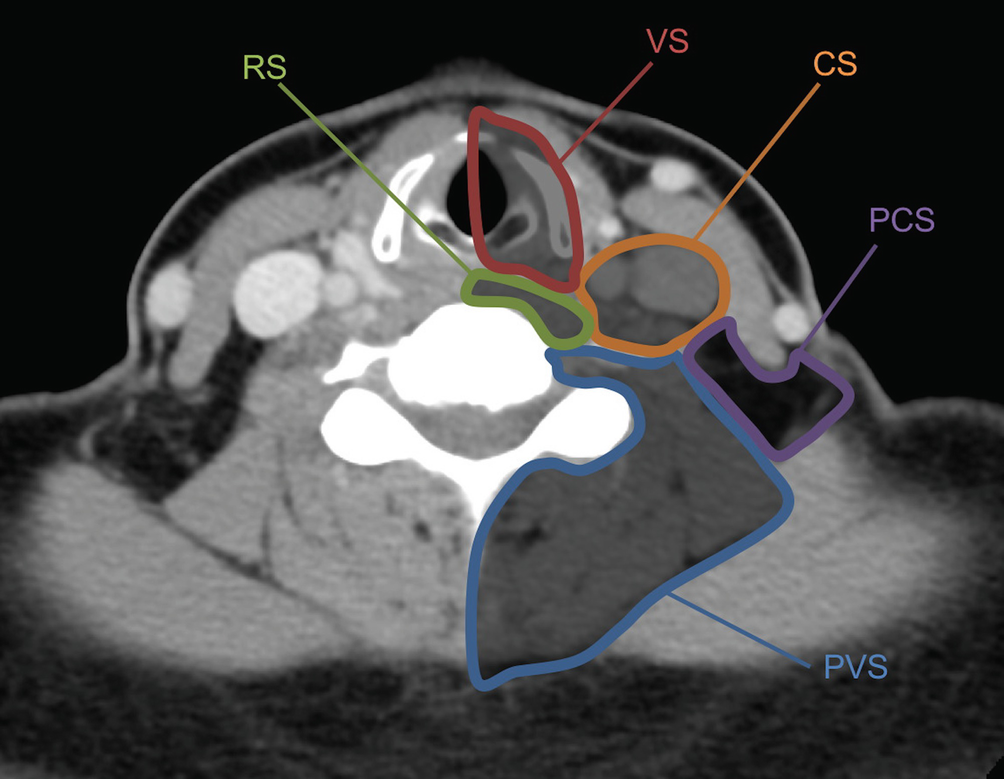

Normal ct exam of the neck soft tissues with iv contrast i will try to go through the comments section to answer any questions this video gives a brief review of the ct scan techniques of neck with ct cross sectional anatomy of the neck spaces. Ct anatomy of skull, axial reconstruction, bone window. Ct neck scan checks the soft tissues of the neck inclusive of the muscles, tonsils, throat, thyroid, airways, adenoids and other glands. Neck, in land vertebrates, the portion of the body joining the head to the shoulders and chest.